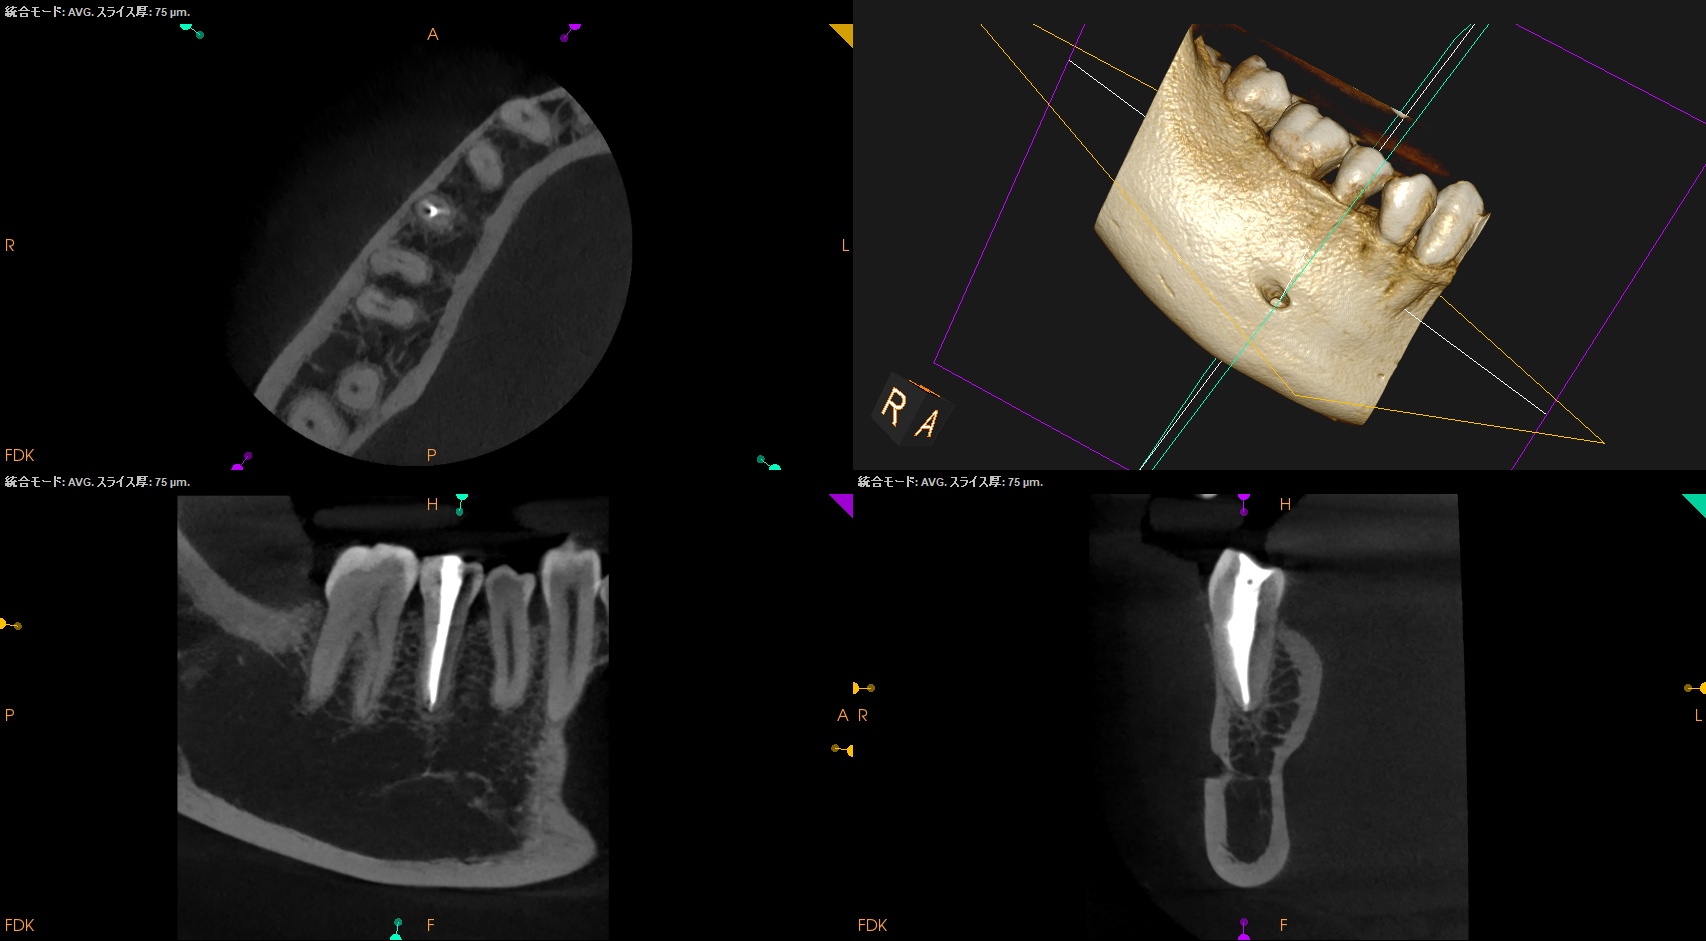

拡大すると、

この根尖部の緑色の部分のせめぎ合いだろう。

根管充填後にPA, CBCTを撮影した。

問題はないだろう。